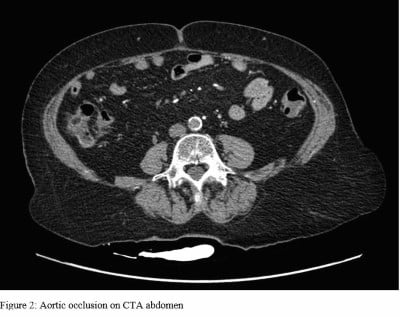

Due to concern for impending limb ischemia, the patient underwent emergent CT angiography studies of the chest, abdomen, and pelvis, which was significant for atherosclerosis and abdominal aortic occlusion extending into the bilateral common iliac arteries (Figures 2 and 3).